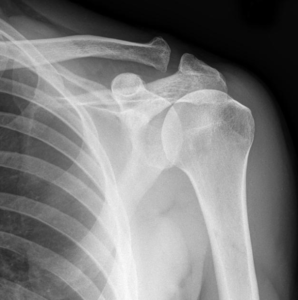

At Surya Diagnostics Center, Nanded City, Pune, we provide advanced diagnostic imaging to help patients and doctors identify and manage shoulder conditions with accuracy and confidence. One of our key imaging services is the X-Ray Shoulder, a simple yet powerful tool used to evaluate shoulder pain, fractures, arthritis, dislocations, and post-surgical conditions.

An X-Ray Shoulder is a non-invasive imaging test that uses a small dose of radiation to produce detailed images of the bones and joints in your shoulder region, including:

The humerus (upper arm bone)

The scapula (shoulder blade)

The clavicle (collarbone)

The acromioclavicular and glenohumeral joints

This imaging helps detect fractures, dislocations, arthritis, infections, or degenerative changes in the shoulder.